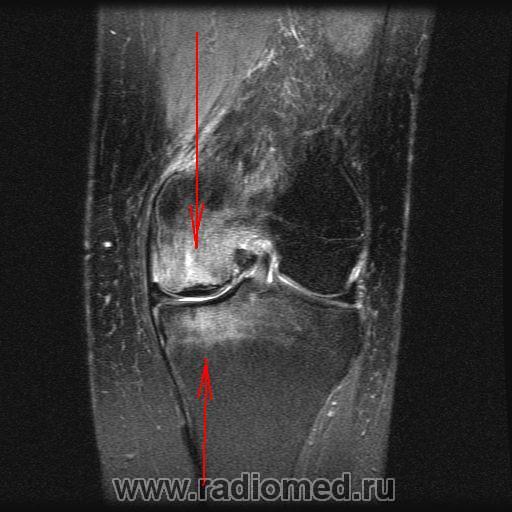

Итак, было выполнено исследование МРТ, которое показало асептический некроз медиального мыщелка бедренной кости и медиального мыщелка большеберцовой кости Также имеются дегенеративные изменения в заднем роге медиального мениска. Передняя и задняя крестообразные связки не повреждены.

"Итак, было выполнено исследование МРТ, которое показало асептический некроз медиального мыщелка бедренной кости и медиального мыщелка большеберцовой кости".

1. Зона асептического некроза сразу в двух костях - медиальный мыщелок б/берцовой кости и медиальный мыщелок бедренной кости, фактически, контактные суставные поверхности двух костей. По всей видимости, такая сочетанная патология, именно в двух костях, на контактных поверхностях не описана даже в литературе, по крайней мере - я не нашел.

Признаться, я и сам удивился несоответствию рентгенологической картины тому, что мы увидели на МРТ (относительно костных структур).

По поводу асептического некроза сразу двух костей -это лишь мое предположение, т.к. я сам встречался, в том числе, в литературе с асептическим некрозом только одной кости, как правило, мыщелка бедренной кости. Но как же тогда объяснить субхондральные изменения и отек большеберцовой кости?

Конечно, можно предположить, что повреждающий фактор (альтерация) действовал, как показано стрелками, т.е. первопричиной все-таки была какая-то травма (надо объяснить контактность поражения). А можт быть это не остеохондропатия?

Глядя на магниторезонансные томограммы, вижу: гвоздь проблемы именно во внутреннем мыщелке бедра. Но, чтобы интерпретировать и, по возможности объяснить картину нам отсталым, нужен иной опыт и знания. Надо звать магниторадиологов.

кроме упомянутых измемений, также отмечается повышение МР-сигнала в заднем рожке медиального мениска - трещина?

Представленные изменения стоит расценивать как результат хронической травматизации мыщелка , вследствие частичной дислокации медиального мениска. Дифференцировать между спонтанным остеонекрозом мыщелка (что чаще встречается в пожилом возрасте) и рассекающим остеохондритом. В любой литературе по МРТ коленного сустава эта патология описана достаточно подробно. Вот у питерских авторов точно описана.

Мне встречались , даже пару раз некрозы медиальных мыщелков обоих костей , в этом случае как правило мениск за пределами суставных поверхностей.

имею не очень большой опыт в ортопедии.., но не думаю что это следует называть некрозом... во всяком случая про большеберцовую кость.

просто выраженный отек костного мозга на фоне травмы мыщелков

Может дело в повреждении гиалинового хряща суставной поверхности , а не в мениске вовсе. Хрящ истончается, повреждается от нагрузки, а потом и кость....

но все равно такой выраженный отек мыщелка бедренной кости видел только после острой травмы, которое не исключается наличием хронического махрового процесса....